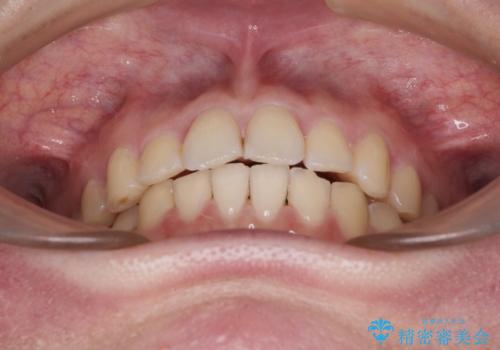

- 食いしばりが気になっていたとのことで来院された患者様です。

当初は睡眠時のマウスピースのみの製作をご希望でしたが、矯正治療の提案をしたところ、インビザラインにて矯正治療を行うこととなりました。

矯正治療中に食いしばりがより強くなることがあるため、半年に1回のペースでボツリヌストキシンによる咬合力緩和を並行して行うこととしました。

咬合力の緩和と食いしばりがちな咬み合わせが改善され、顎の負担が大幅に軽減されました。